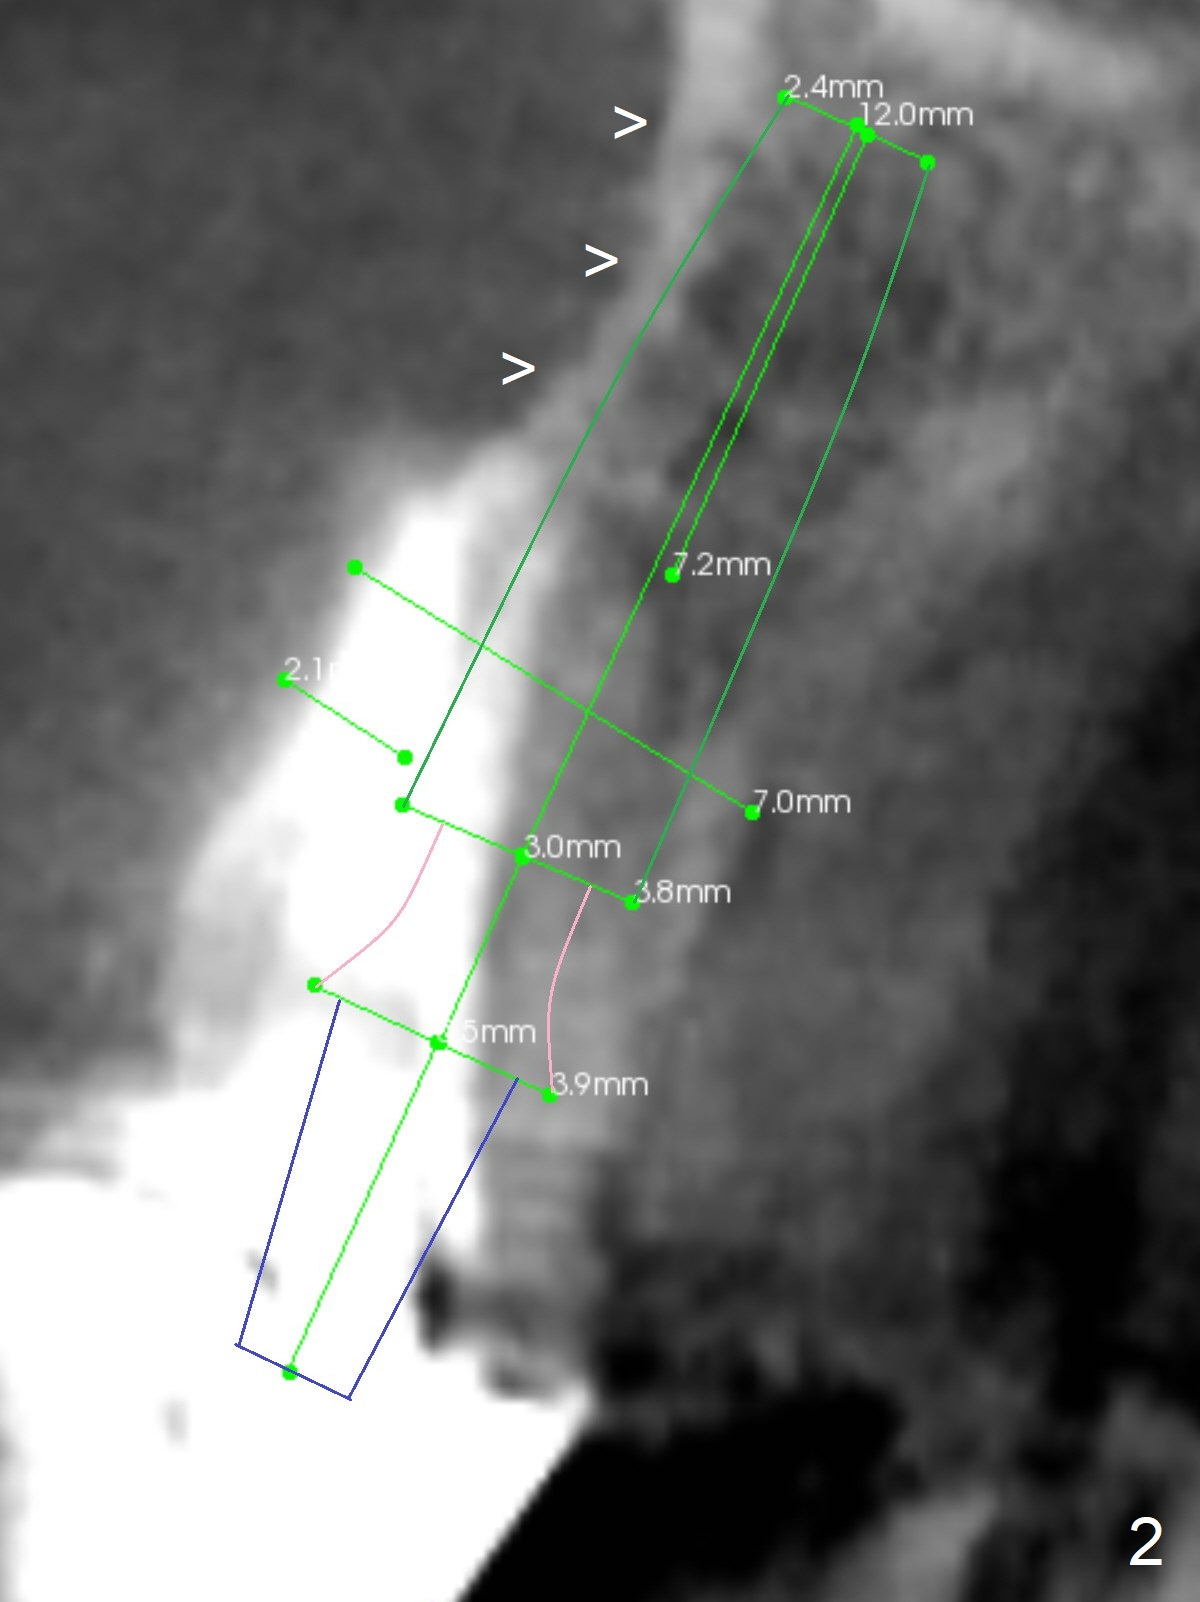

A 37-year-old woman needs an implant at #10 because of crown recementation twice (Fig.1). The smallest 2-piece implant, 3.8 mm, appears to be larger than the root. The implant may perforate the buccal apical concavity (Fig.2 arrowheads). Measure the extracted root. If it is wider than 3.8 mm mesiodistally, place the 2-piece implant. Otherwise use a 3 mm 1-piece one. Do not forget the angled one. Retrospectively, the 3.8 mm implant is large for the site. A 3.0 or 2.5 mm one is more appropriate (Fig.2).